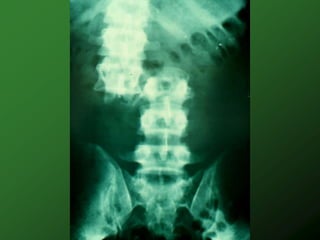

Other Complications

 Heterotopic ossification

(ROM)

 Osteoporosis (DEXA)

Other Complications  UTI,stones, renal failure (annual US, BUN/Cr)  Heterotopic ossification (ROM)  Osteoporosis (DEXA)  Bowel obstruction,